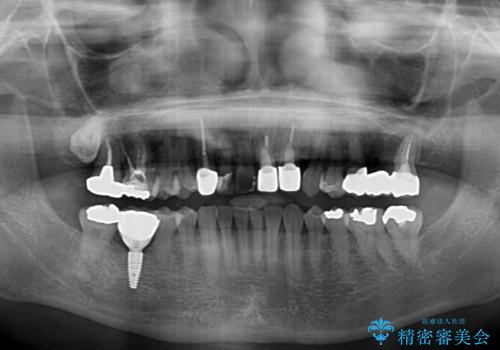

上下非接触の咬み合わせは、舌突出癖によるところが大きく、トレーニングを行いながら治療を進めていきました。

なかなか突出癖が改善できず、過剰歯を抜歯したスペースを閉じるまでに時間がかかりました。

舌突出癖の改善は、治療期間や仕上がりに大きな影響を与えるため、しっかりとトレーニングすることが大切です。